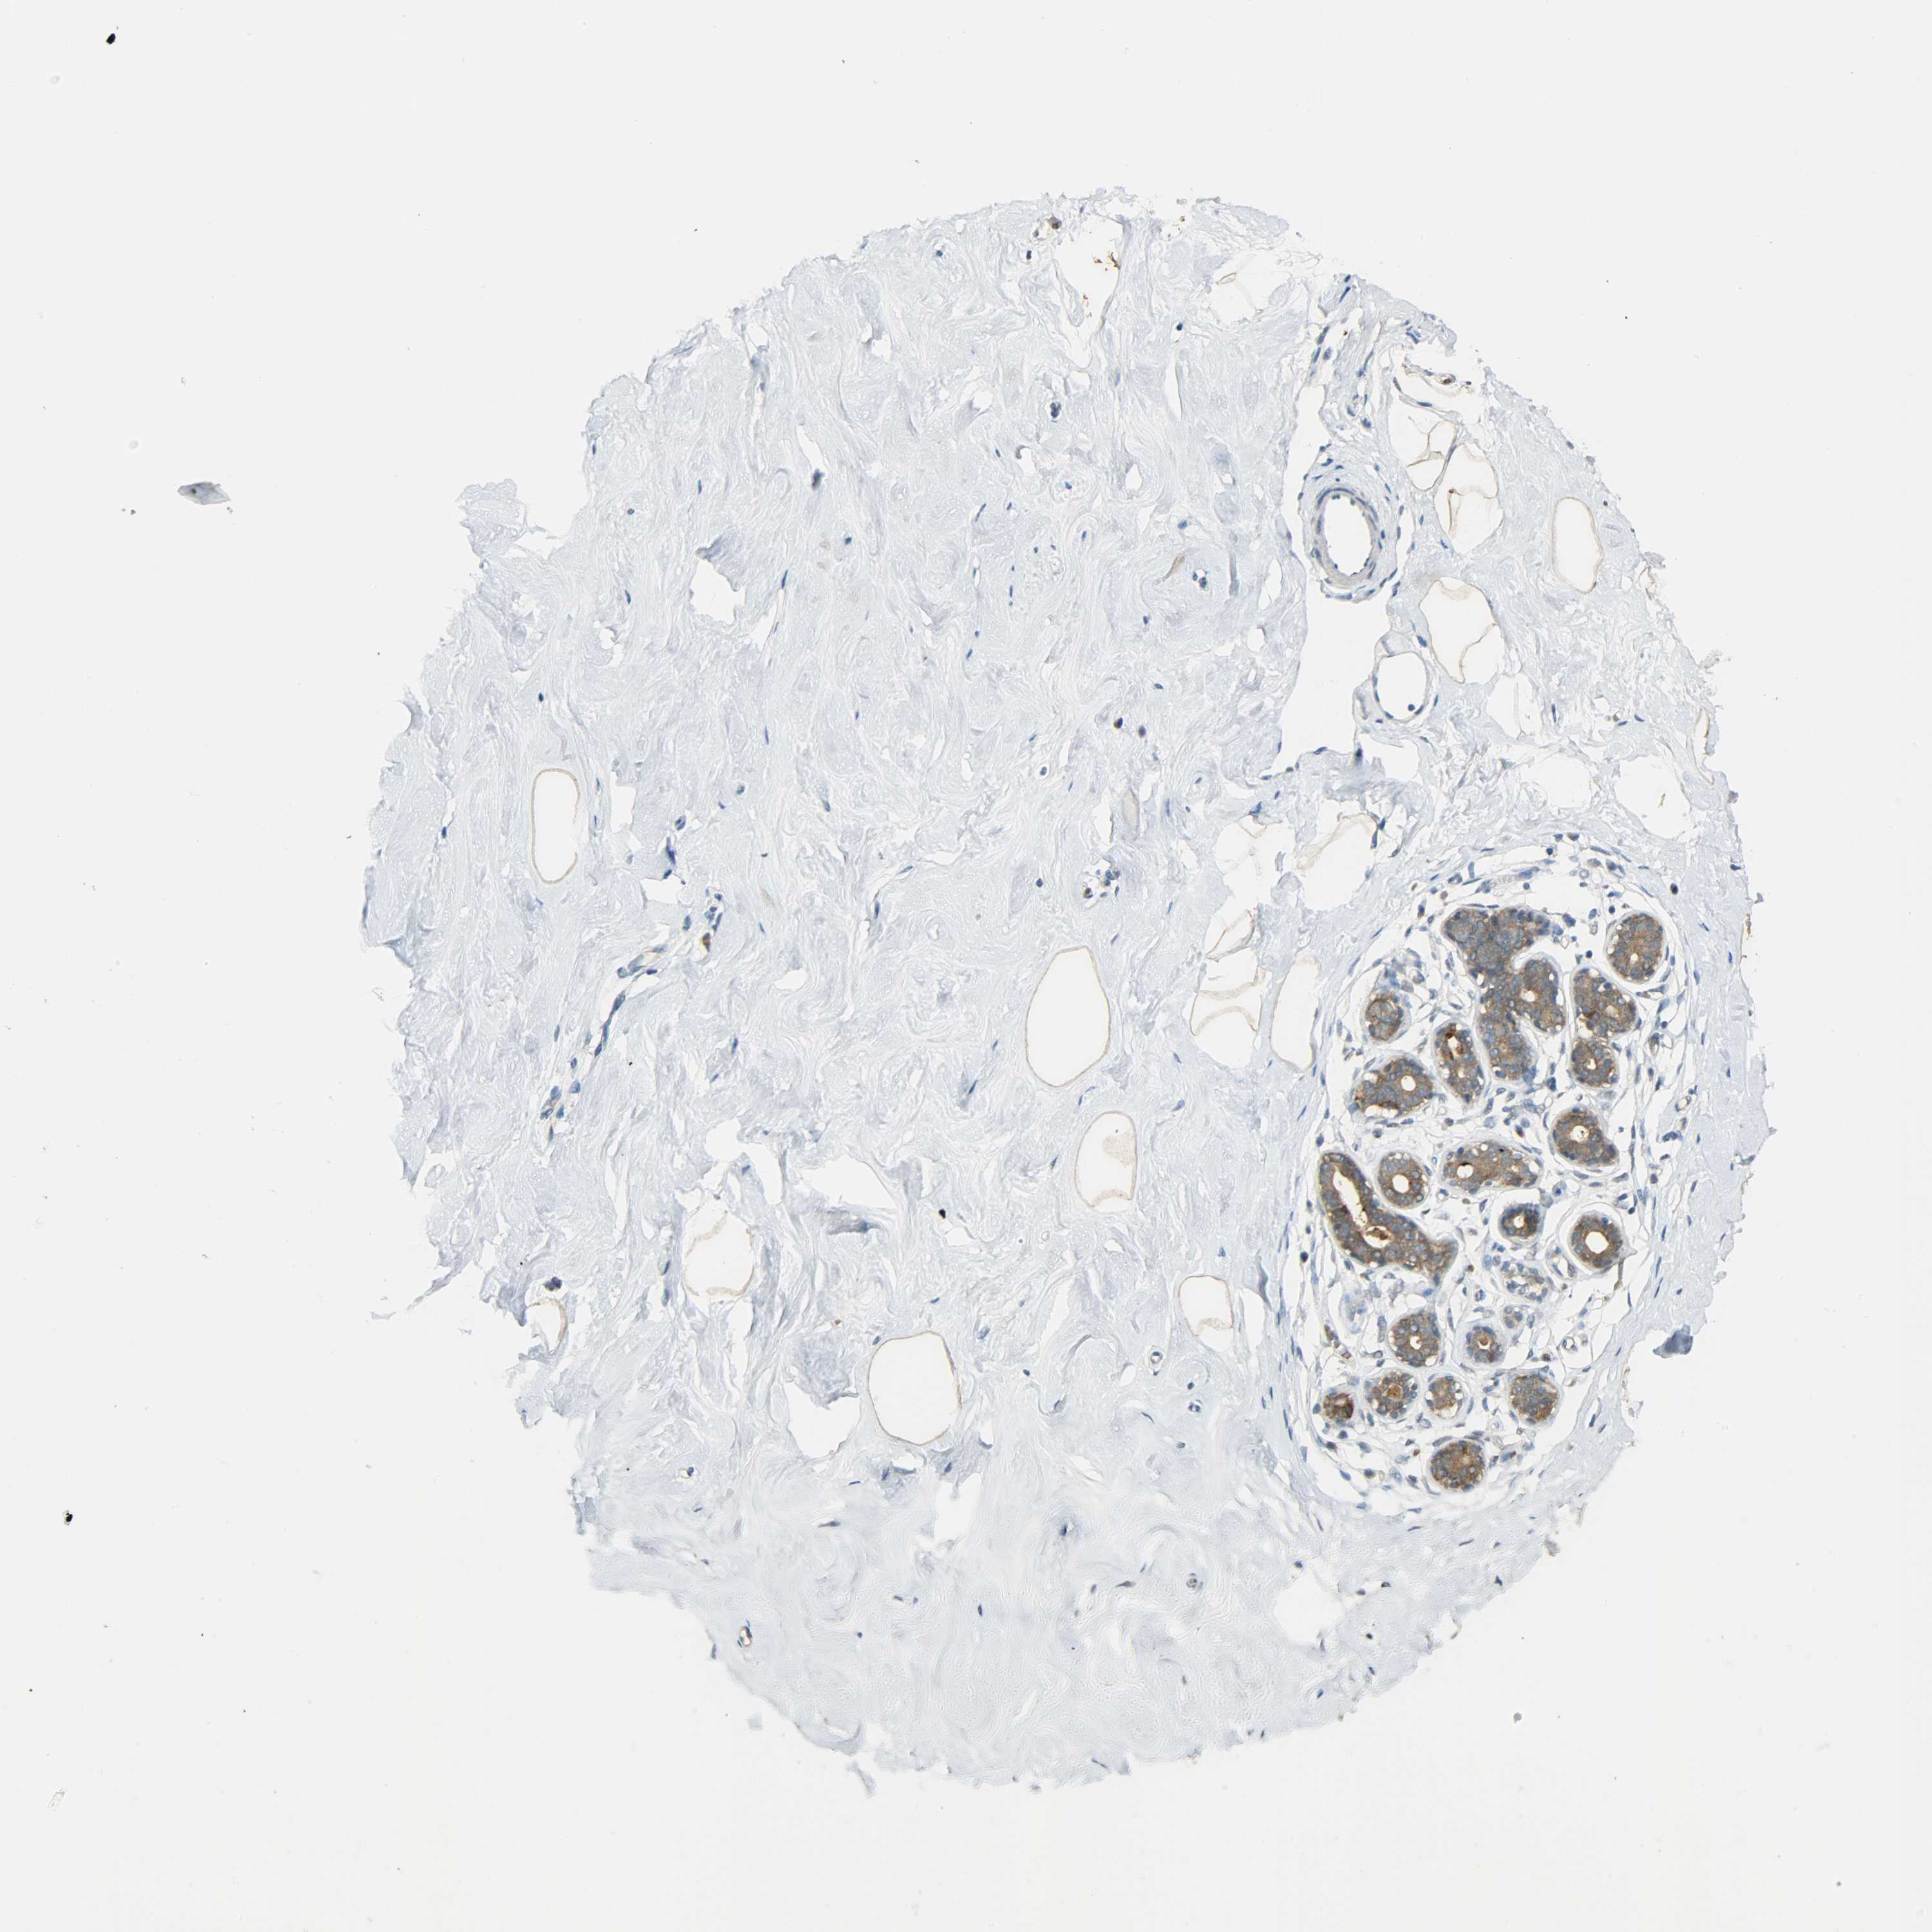

Antibody staining in the annotated cell types in the current human tissue is reported as not detected, low, medium, or high. This score is based on the staining intensity and fraction of stained cells.

Information about each individual sample is listed below, including gender, age, a tissue section image and estimated fractions of cell types. pTPM (transcripts per million) values give a quantification of the gene abundance which is comparable between different genes and samples.

Glandular cells: 5 Adipocytes: 5 Other cell types: 90

Female, age 38

Breast sample 410 pTPM: 74.1

Cell types%